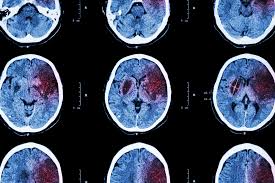

• термінова комп’ютерна томографія або магнітно-резонансна томографія,